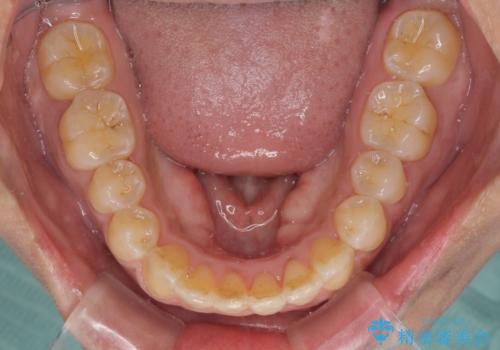

インビザラインによる狭窄歯列の拡大矯正

上下顎ともに歯列全体の後方移動と側方拡大、IPR(歯と歯の間を削る)によってデコボコが解消するように設計し、インビザラインにより治療を行うこととしました。

治療途中で関西に転勤となってしまったため、東京に出張で来るタイミングに合わせて治療を進めることになりました。そのため、治療期間が長くなってしまいましたが、無事に仕上げることができました。